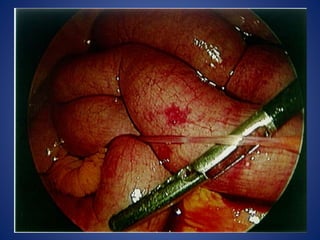

RADIOGRAPHY

OPERATIVE MANAGEMENT

•REDUCING THE TERMINAL PART OF THE INTUSSUSCEPTION :

•REDUCING IS ACHIEVED BY SQUEEZING THE MOST DISTAL PART OF THE MASS IN

CEPHALAD DIRECTION